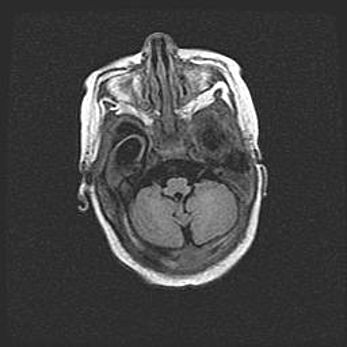

Мальформация Денди-Уокера. Киста задней черепной ямки.

Агенезия мозолистого тела.

Возраст: 2,5 месяца

Вес: 2420 г

Пол: женский

Окружность головы: 37 см

Срок гестации: 32 недели

Мальформация Денди—Уокера — редкий вид патологии ЦНС, представляющий собой врожденный порок развития каудального отдела ствола и червя мозжечка, ведущий к неполному раскрытию срединной (Мажанди) и латеральных (Лушка) апертур IV желудочка мозга. Для этогно синдрома характерна триада симптомов: гипотрофия червя мозжечка и/или полушарий мозжечка, кисты задней черепной ямки, гидроцефалия различной степени. В 70% случаев порок сочетается и с другими аномалиями головного мозга, в частности с агенезией мозолистого тела.